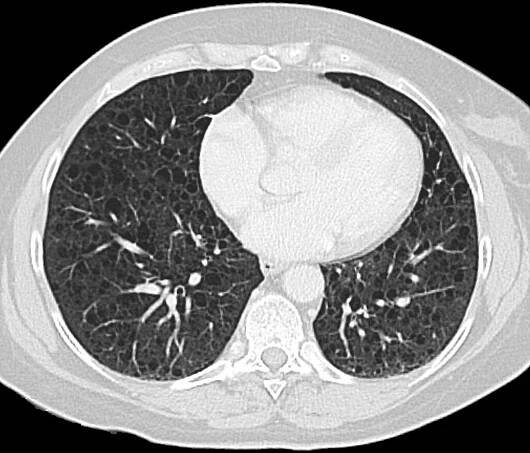

Na CT plic se zobrazil nález - ložisko S 10 L plíce vel až 10 cm. Po přečtení snímků plicním odborným lékařem, byla potvrzena výrazná arterie odstupující z hrudní aorty směrem k centru ložiska ( jde o cystu s tekutinou), byl vyvrácen…